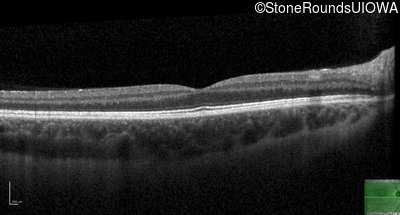

Leber Hereditary Optic Neuropathy (IIIC1c)

Age at visit: 22 years

This 22 year old man first noticed blurry vision, more so in the right eye than the left, about 6 months ago.

Diagnosis & molecular findings

Leber Hereditary Optic Neuropathy MT-ND4 11778 A>G   MT